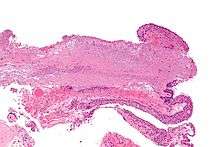

Pathology

Pterygium in the conjunctiva is characterized by elastotic degeneration of collagen (actinic elastosis[6]) and fibrovascular proliferation. It has an advancing portion called the head of the pterygium, which is connected to the main body of the pterygium by the neck. Sometimes a line of iron deposition can be seen adjacent to the head of the pterygium called Stocker's line. The location of the line can give an indication of the pattern of growth.